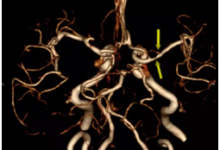

CT血管成像(CTA)最早报道于1992年,是一种将螺旋CT扫描和图像后处理相结合以显示血管及其病理生理改变的无创影像技术。随着技术创新和研究的推进,CTA在很大程度上替代了传统的有创性血管造影,成为大多数心血管疾病的首选检查方法。本文概述了CTA的早期发展及其演变历程,总结了CTA研究领域的前沿技术——冠状动脉CTA的新进展,如CT血流储备分数、CT心肌灌注等的应用,探讨了继续提升CTA的临床转化应用的路径以及展望了CTA的未来。